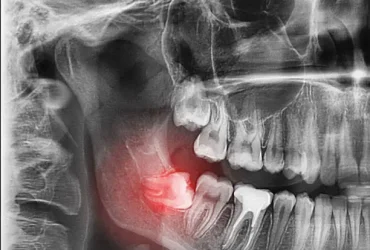

ฟันคุดคือ อะไร

ฟันคุดคือ ฟันกรามซี่ในสุด ทั้งหมด 4 ซี่ บน ล่าง ซ้าย ขวา ไม่สามารถขึ้นได้ตามปกติเพราะพื้นที่ไม่เพียงพอให้ฟันสามารถขึ้นมาได้ บางซี่อาจจะโผล่ขึ้นมาเล็กน้อย และบางซี่ถูกฝั่งอยู่ในกระดูดขากรรไกร อาจจะขึ้นตรง เอียงหรือนอนในแนวราบส่วนใหญ่ฟันคุดมักพบว่าอยู่ที่ฟันกรามซี่ล่างในสุดและพบมากสุดในช่วงอายุ ประมาณ 16 – 25 ปี หรืออาจจะช้ากว่านั้น

ทำไมต้องผ่าฟันคุด

เพื่อป้องกันปัญหาเกี่ยวกับช่องปาก ฟันผุ เหงื่อกอักเสบ ฟันซ้อมเก ไม่ควรปล่อยให้ฟันคุดฝั่งอยู่ในขากรรไกร เพราะอาจะทำให้แนวฟันอื่นเสียหายจากการดันตัวของฟันคุด และที่สำคัญคือส่งผลให้มีอาการปวดฟันคุดรุนแรง